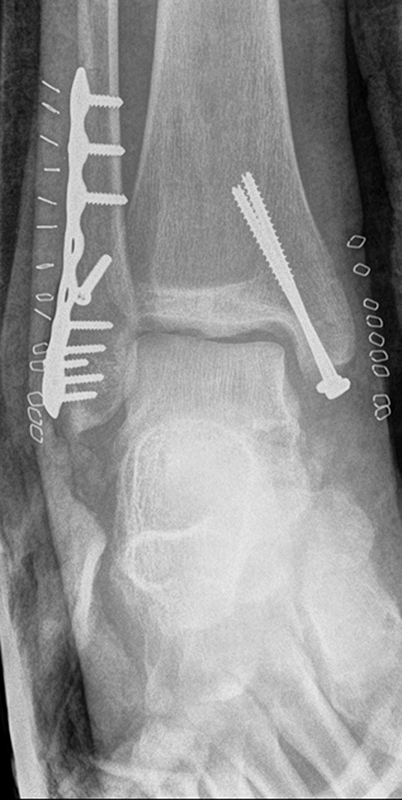

Seit einer Untersuchung von Nelson und Jensen aus dem Jahre 1940 wird allgemein akzeptiert, dass die Indikation zur Osteosynthese des Tibiahinterkantenfragments nur dann besteht, wenn die Größe mehr als ein Drittel (nach zahlreichen Autoren auch ein Viertel) der Gelenkfläche beträgt (Abbildung 15) 25. Dieses bis heute allgemeinakzeptierte Vorgehen basiert auf der Beobachtung von lediglich acht unterschiedlich versorgten Patienten. Seither gibt es keine weiteren klinischen Studien, die dieses Vorgehen stützen. Mittlerweile gibt es allerdings zunehmend Hinweise, dass bei der Versorgung des posterioren Malleolus viele andere Faktoren eine wichtige Rolle spielen 26. Da an der Tibiahinterkante das Lig. tibiofibulare posterius ansetzt (Abbildung 16), wird durch die offene Reposition und Stabilisierung die Integrität und die physiologische Spannung der hinteren Syndesmose rekonstruiert (Abbildung 17). Dies ist entscheidend für die anatomische Reposition der Fibula in der Tibiainzisur.

Gardner et al. konnten beispielsweise zeigen, dass die offene anatomische Reposition der Tibiahinterkante der Stabilisierung mittels Stellschraube überlegen war und gleichzeitig mit einer geringeren Rate an postoperativen Fehlstellungen der Fibula in der CT-Kontrolle einherging 2728. Aus Sicht der Autoren ist prinzipiell die Stabilisierung über eine direkte Reposition indiziert, wenn die Größe des Fragmentes dies erlaubt. Bei gleichzeitigem Vorliegen einer Fraktur des lateralen und/oder medialen Malleolus sollte zunächst die Versorgung der des Tibiahinterkantenfragments erfolgen. Dies erlaubt die radiologische Kontrolle der Reposition und Osteosynthese-Lage, welche durch eine zuvor aufgebrachte Fibula-Platte häufig erschwert ist 29. Dafür werden die Patienten in Seitenlage gelagert. Dies erlaubt die direkte Versorgung der posterioren Malleolusfraktur über einen posterolateralen Zugang 30. Das sehr kräftige Periost wird im Frakturverlauf inzidiert und aus den Frakturspalt entfernt, so kann eine anatomische Reposition erfolgen. Entsprechend der Fragmentgröße erfolgt entweder die Versorgung mittels Drittelrohrplatte in Antiglide-Technik oder eine Zugschraubenosteosynthese. Die Versorgung der Fibula-Fraktur gelingt über den gleichen Zugang. Zur Versorgung des medialen Malleolus wird der Patient auf den Rücken umgelagert. Dies kann bei entsprechender Vorbereitung ohne erneutes steriles Abdecken erfolgen. Durch dieses Vorgehen konnte im eigenen Kollektiv die Notwendigkeit einer Stabilisierung der Syndesmose mit Stellschraube/Tight Rope deutlich reduziert werden.